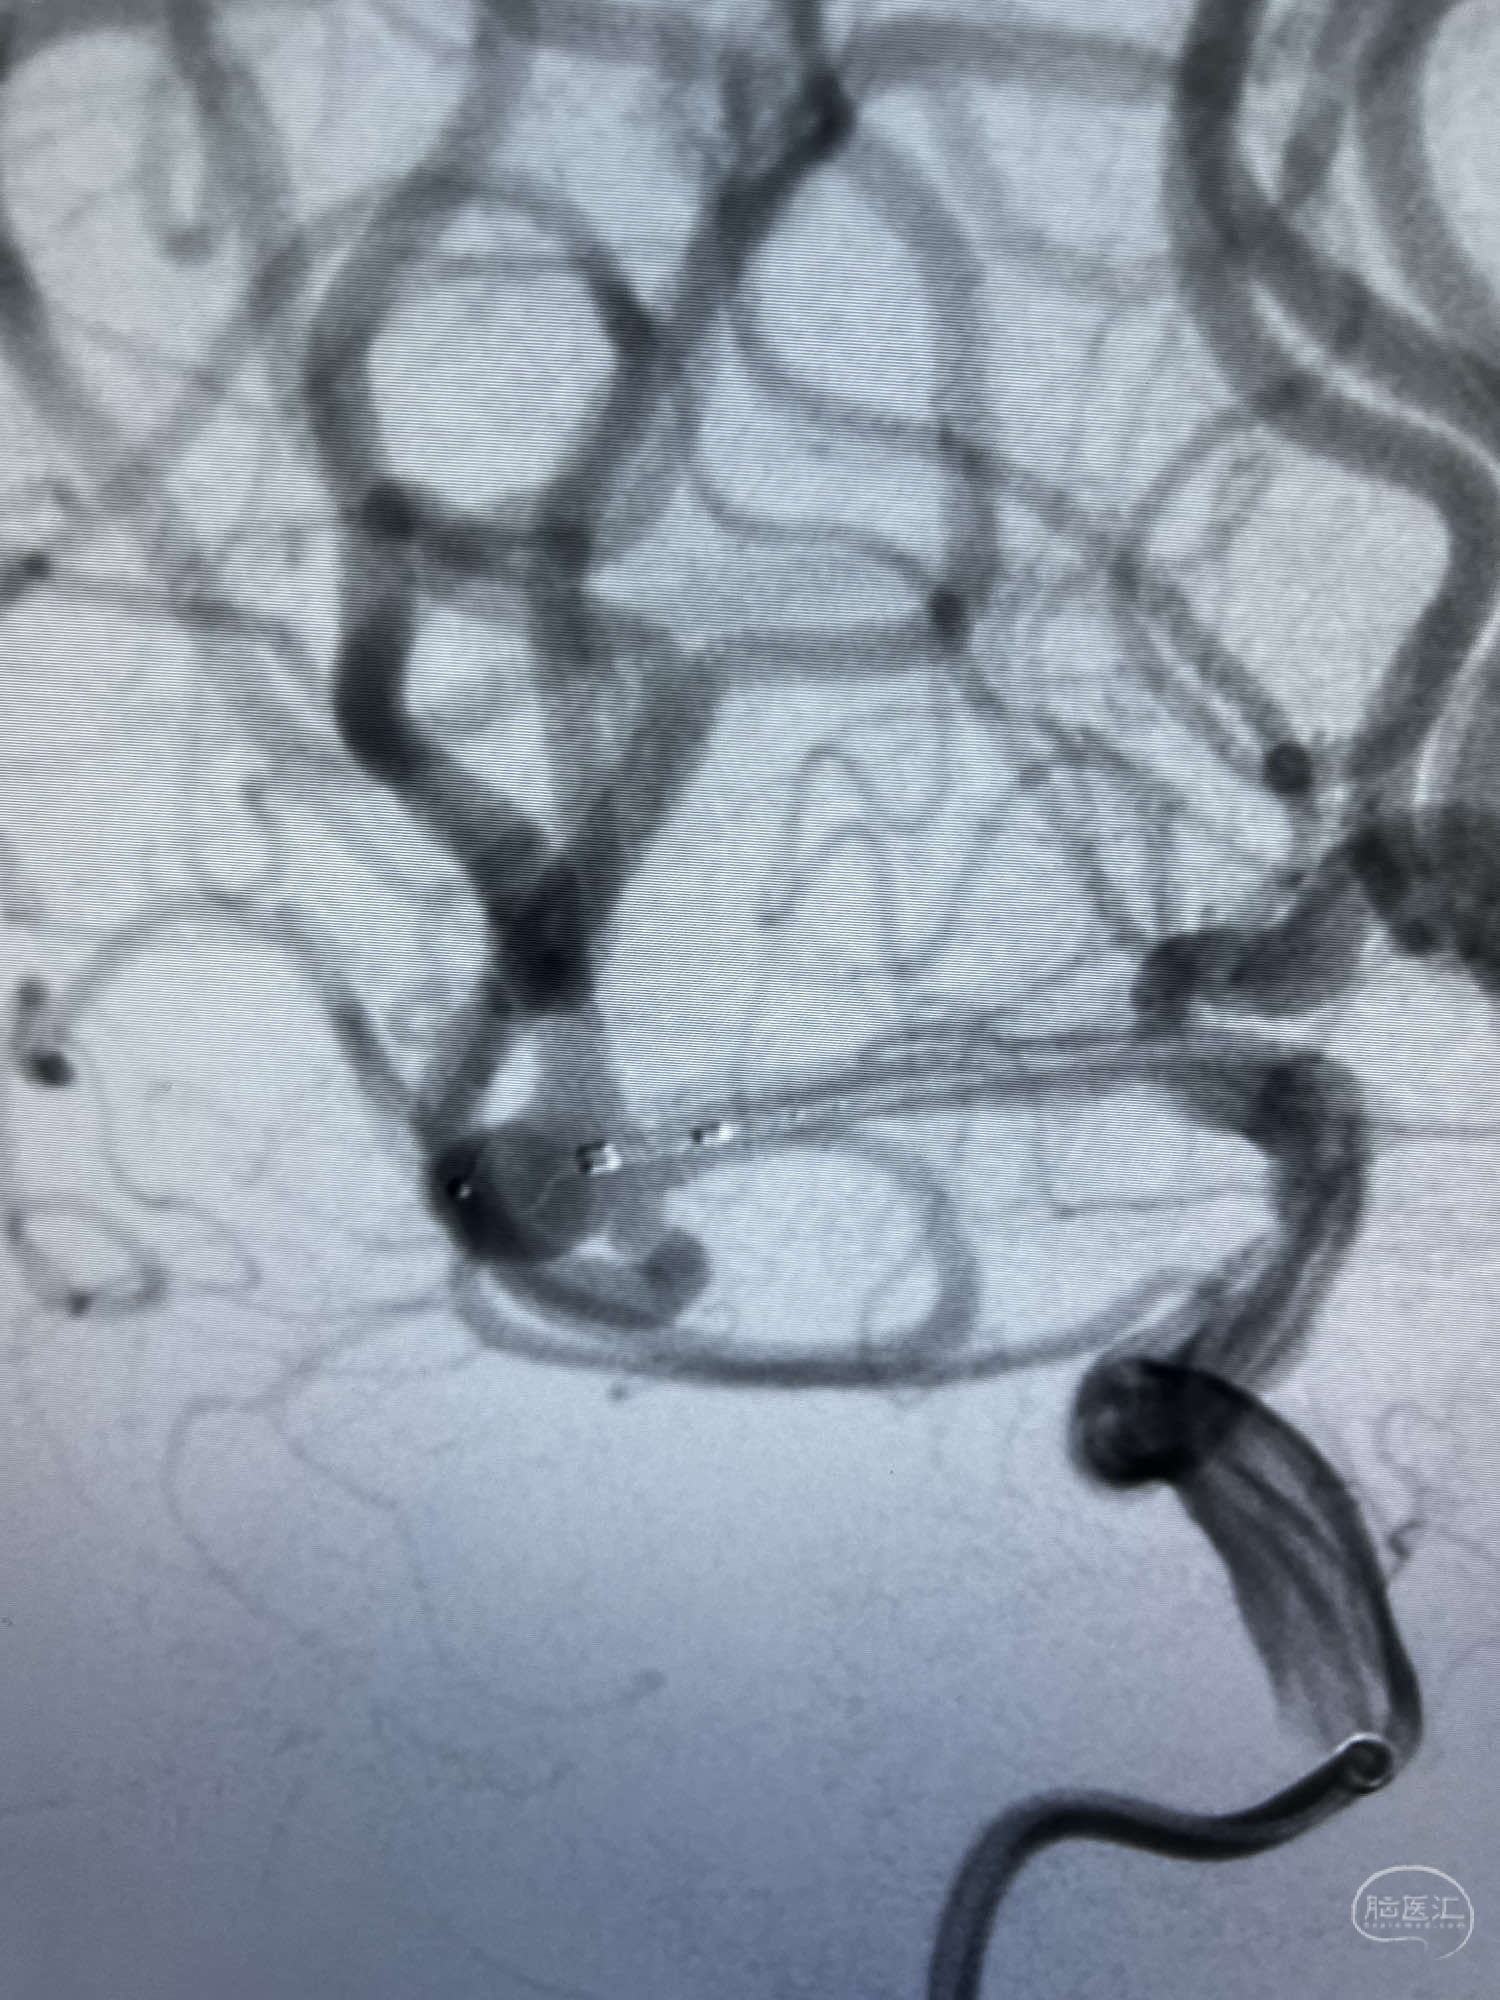

DSA示:左侧颈内动脉眼动脉段以远闭塞,后交通动脉开放,椎基底动脉通过后交通动脉代偿左侧大脑中动脉区域,右侧发出双侧大脑前动脉,右侧大脑中动脉M1末端宽颈动脉瘤,大小约4.3mmx4.6mm。

WEB瘤内扰流装置5mmx3mm经过“种子、萌芽、开花”三个阶段,打开后良好贴壁,动脉瘤内血液滞留,载瘤动脉通畅。WEB一步到位,通过瘤内扰流的方式起到栓塞动脉瘤的作用,避免了应用支架保护分支血管,简化了操作步骤,降低了术中血栓及出血的风险。